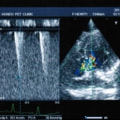

症例1:閉塞型肥大型心筋症(HOCM)【アメリカン・ショートヘア 4歳齢 去勢オス】

D:超音波写真 狭窄部の異常血流速度の測定

1年ほど前より左側胸壁からLevine 3/6の心雑音が聴取されていた。雑音の精査のため、心エコー検査を行ったところ、左室流出路の狭窄を伴う肥大型心筋症(閉塞型肥大型心筋症)と判明した。心室の拡張性を上げるため、βブロッカーであるカルベジロールを用いた治療を行っている。肥大型心筋症は犬の心疾患のように、心拡大を認めないことも多く、レントゲン写真のみで心疾患の有無を判断する事が出来ない。また、閉塞を伴わない肥大型心筋症と異なり、閉塞型の本疾患の治療に対し、Caチャネルブロッカーは推奨されない。